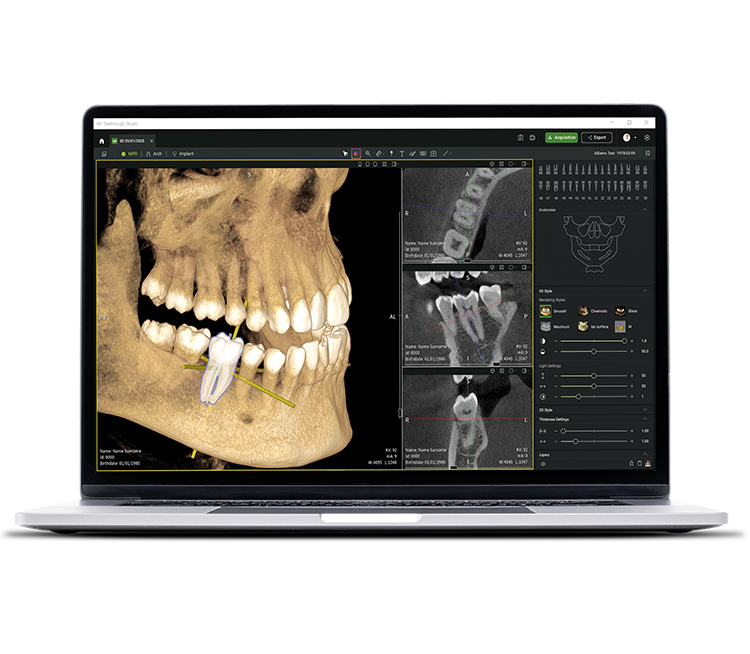

• Seethrough Studio

See tomorrow. See a new level.

In addition to sophisticated hardware technologies, the revolutionary Seethrough Studio software is a decisive factor for the high standard of the entire W&H imaging portfolio. With its beneficial features and advanced algorithms, Seethrough Studio is an all-in-one solution that takes imaging quality and digital dentistry workflows to a new level.

Implant planning tool integrated

In addition to the outstanding image quality and intuitive operation, Seethrough Studio offers numerous useful features such as the standard integrated implant planning tool for easy visualisation and preparation of the treatment.

AI-supported functions

Seethrough Studio utilises various AI tools for imaging enhancement, including 3D volume alignment, tooth segmentation, arch line generation, automatic nerve tracing as well as useful support for pathology detection.